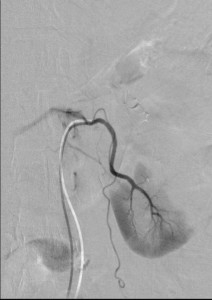

Consider a formal digital subtraction angiography when the above measures did not help you figure out the cause. Angiography can offer information about small branches of the renal artery that computed tomography and MRA cannot. Sometimes, the only way to make the diagnosis of fibromuscular dysplasia or segmental arterial mediolysis is with angiography. However, it must be noted that the angiography is most useful soon after the event. If you wait, the picture may no longer be clear. For instance, you may not be able to see an artery dissection. Still, the earliest time after the infarction is unfortunately also when it is most risky.